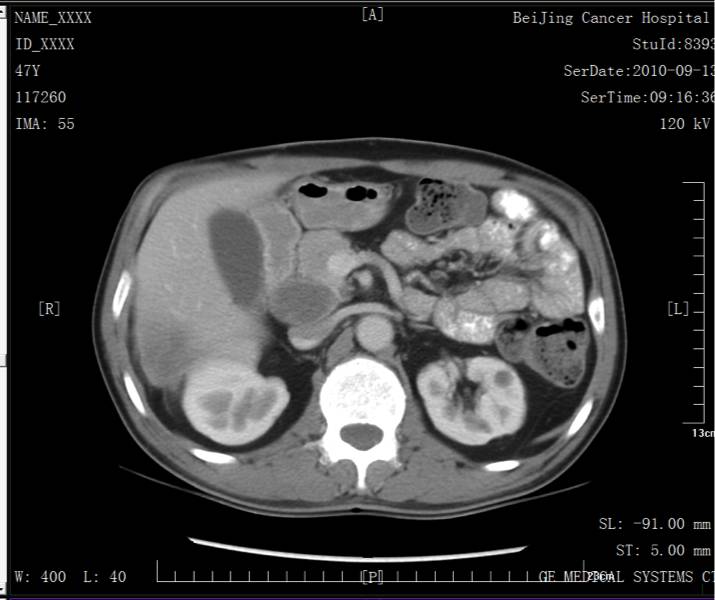

2010.09.06腹部超声复查发现腹膜后低回声肿大淋巴结,大小约4.7x2.6x4.0cm。

第三次手术(淋巴结)

2010.09.20在全麻下行腹膜后肿物切除术。术中探查肿瘤位于胰头后,质硬,大小约3cm,胆总管下段及胰头关系密切。因行R1切除,在该处放置钛钉。作为术后放疗标记,待术后放疗使用。术后病理:淋巴结可见低分化腺癌浸润伴大片坏死(1/1)。